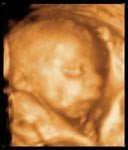

La ecografía en 3 dimensiones o la 4D (3 dimensiones en movimento) es la mejora en la calidad de la imagen proyectándola en más dimensioens, da una imagen más real del feto pero no es más sensible a la hora de descartar ciertas anomalías que la bidimensional.

Aparte del punto de vista médico, es el primer contacto que tienen los padres con el bebé, le ven moverse, succionar, a veces hasta bostezar, asi que también es muy importante desde el punto de vista emocional.